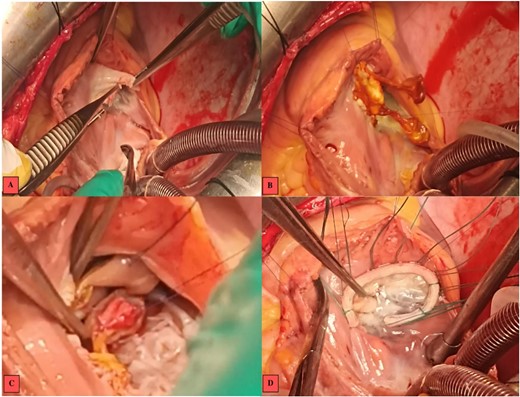

Intraoperative images. (A) Vegetations on the anterior tricuspid leaflet. (B) Valvular suture of the mitral autograft to the native tricuspid annulus. (C) Suture of the anterior papillary muscle of the mitral autograft to the interventricular septum. (D) Tricuspid annuloplasty ring with no residual regurgitation at serum testing.